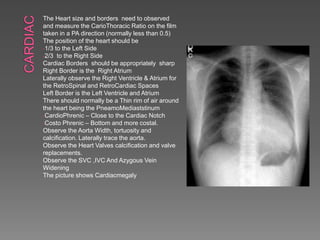

 C - Cardiac

 Check heart size and heart borders

 Heart position –⅔ to left, ⅓ to right

 Heart size – measure cardiothoracic ratio on PA

film (normal <0.5)

 Heart borders – R) border is R) atrium, L)

border is L) ventricle & atrium

 Appropriate or blunted

 Thin rim of air around the heart, think of

pneumomediastinum

 Trace the aorta

The Heart size and borders need to observed

and measure the CarioThoracic Ratio on the film

taken in a PA direction (normally less than 0.5)

The position of the heart should be

-1/3 to the Left Side

-2/3 to the Right Side

Cardiac Borders should be appropriately sharp

Right Border is the Right Atrium

Laterally observe the Right Ventricle & Atrium for

the RetroSpinal and RetroCardiac Spaces

Left Border is the Left Ventricle and Atrium

There should normally be a Thin rim of air around

the heart being the PneamoMediaststinum

-CardioPhrenic – Close to the Cardiac Notch

-Costo Phrenic – Bottom and more costal.

Observe the Aorta Width, tortuosity and

calcification. Laterally trace the aorta.

Observe the Heart Valves calcification and valve

replacements.

Observe the SVC ,IVC And Azygous Vein

Widening

The picture shows Cardiacmegaly